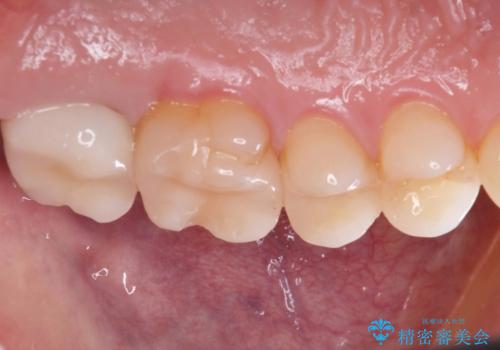

【メタルフリー】銀歯を綺麗な白い歯に

一番奥の歯は銀歯に覆われている範囲が多いため、強度などを踏まえ被せ物にしました。

その他2本は詰め物です。

銀歯が綺麗な白い歯になりました。

適合がとてもよいので、フロスの引っかかりも解消されました。